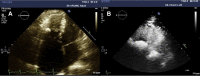

Tropical endomyocardial fibrosis is a common cause of restrictive cardiomyopathy worldwide, but is relatively rare in developed countries. We present a case of tropical endomyocardial fibrosis with right ventricular involvement initially mistaken as Ebstein's anomaly. We highlight the need for timely and accurate diagnosis to ensure appropriate management. (Level of Difficulty: Intermediate.).